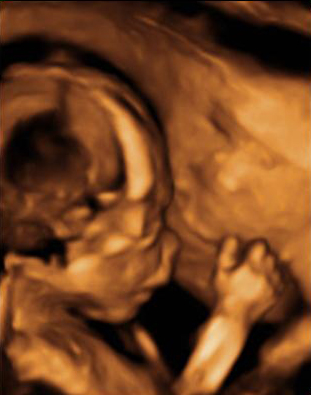

Las ecografías en 2D y en 3D en la semana 20 de embarazo permite diagnosticar algunas malformaciones congénitas fetales, como el labio leporino, que se visualiza en estas imágenes.

Labio leporino (*)

Visualización del mismo caso con ecografía 2D (izquierda) y con ecografía 3D (derecha). La imagen más evidente en la ecografía 3D hace más comprensible para los padres el alcance del problema.